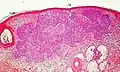

Nodular basal-cell carcinoma

.jpg.webp)

Nodular basal-cell carcinoma (also known as "classic basal-cell carcinoma") accounts for 50% of all BCC.[21] It most commonly occurs on the sun-exposed areas of the head and neck.[22]: 748 [23]: 646 Histopathology shows aggregates of basaloid cells with well-defined borders, showing a peripheral palisading of cells and one or more typical clefts.[21] Such clefts are caused by shrinkage of mucin during tissue fixation and staining.[24] Central necrosis with eosinophilic, granular features may be also present, as well as mucin. The heavy aggregates of mucin determine a cystic structure. Calcification may be also present, especially in long-standing lesions.[21] Mitotic activity is usually not so evident, but a high mitotic rate may be present in more aggressive lesions.[21] Adenoidal BCC can be classified as a variant of NBCC, characterized by basaloid cells with a reticulated configuration extending into the dermis.[21]

Cleft.